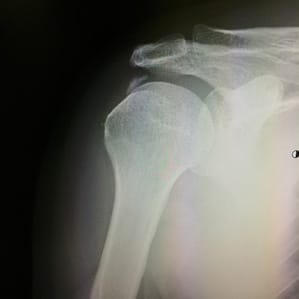

腱板断裂

転倒や落下など1回の大きな外傷、または小さな外傷が繰り返されることで生じます。その他、加齢と共に変性した腱板が、肩を動かす際に引っぱられることによっても切れることがあります。診断は診察の他、レントゲン、超音波検査、MRIなどで行います。症状としては、夜間の痛みで寝られなかったり、運動時の痛みのため腕が上がりにくくなったりします。消炎鎮痛剤(内服薬、外用薬)の使用、関節内注射などの治療法があり、強い痛みが軽くなれば、温熱治療や可動域訓練、筋力強化などを行います。また、これらの治療を行っても痛みが続く場合や損傷が激しい場合は手術治療を行うことがあります。

外傷によるもの

上腕二頭筋長頭腱の断裂などの腱損傷、上腕骨近位端骨折や肩甲骨骨折、鎖骨骨折などの骨折、肩関節脱臼や肩鎖関節脱臼などの脱臼などが考えられます。